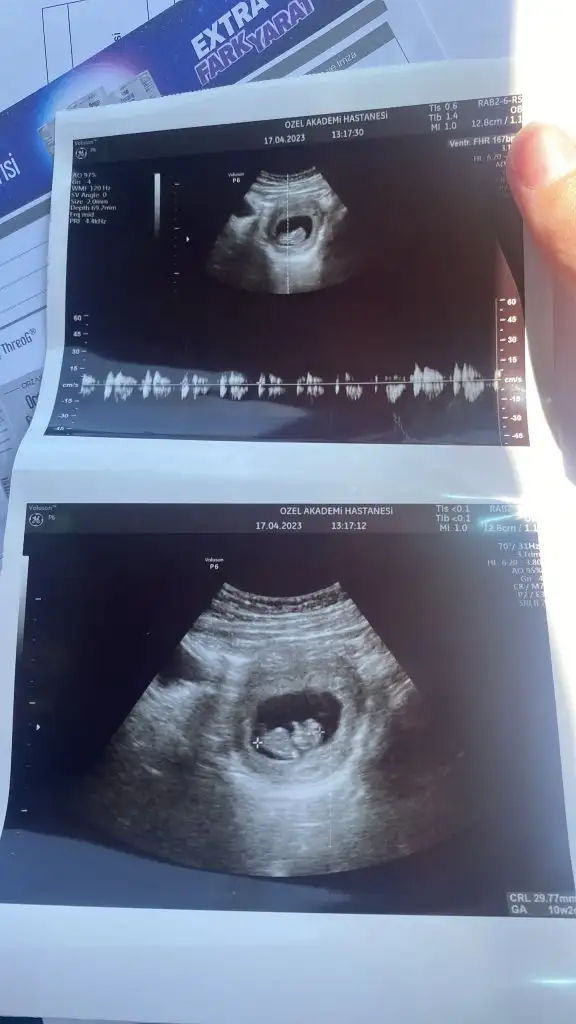

doktor da bulunmustur diye dusunuyorum. tatli bi kiziniz olacak allah bağışlasın.Bana da tahminlerde bulunur musunuz 11+6 yız

Bu kız ya. Bacak arasındaki çizgi yatay ve iki çizgi görünüyor. Net olmadığı için 3 çizgi görünmemişBana da tahminlerde bulunur musunuz 11+6 yız

Doktor da kız dedi evetBu kız ya. Bacak arasındaki çizgi yatay ve iki çizgi görünüyor. Net olmadığı için 3 çizgi görünmemiş

Cnm kesin kız mı?Doktor da kız dedi evet![]()